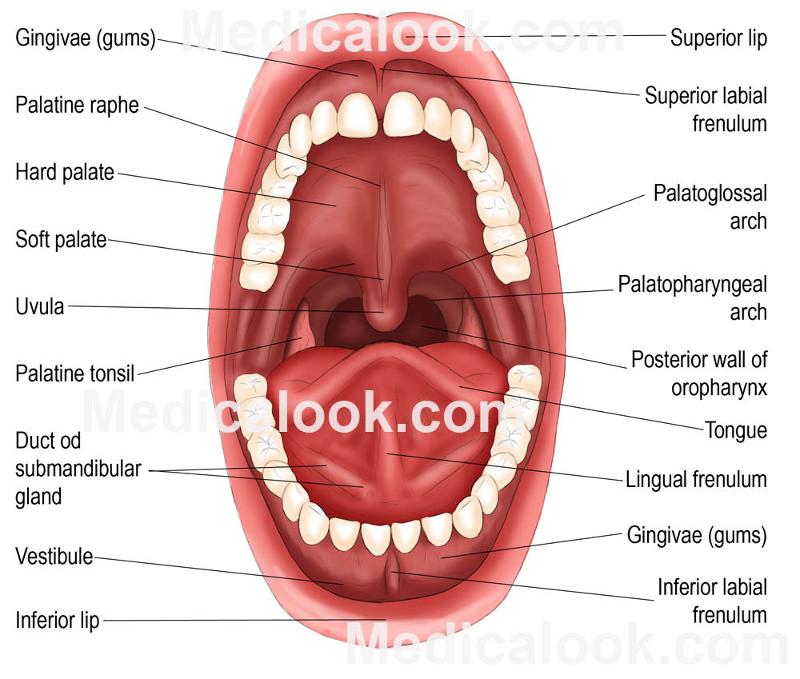

Oral Cavity (Buccal)

Hard Palate

Soft Palate

Vestibule

Uvula

Frenulum